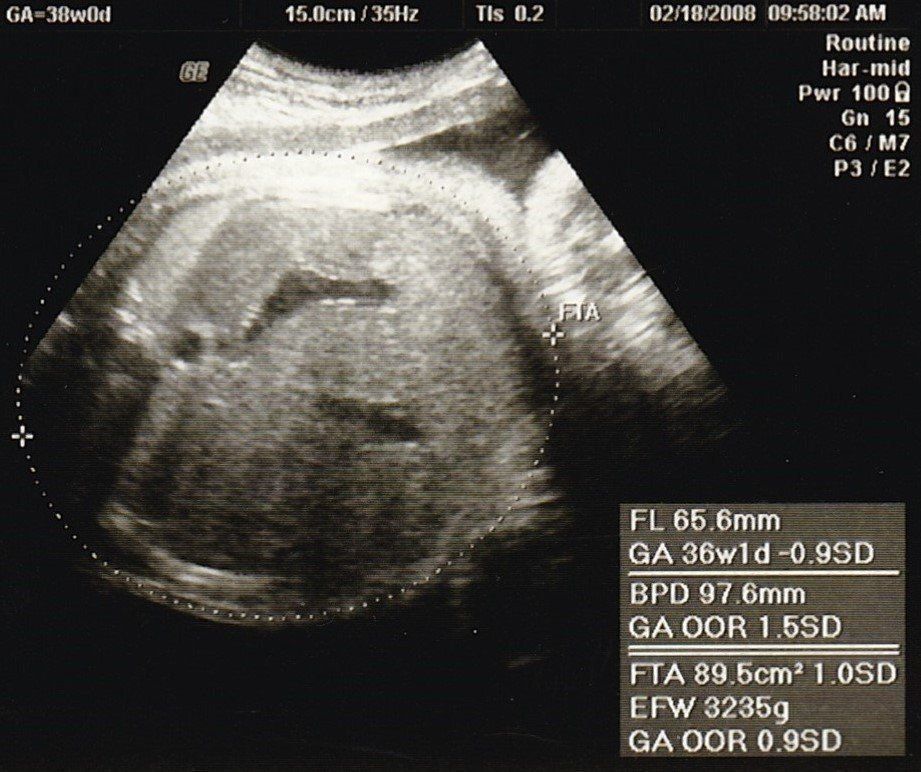

妊娠38週目のエコー写真

このころ、ママ友から続々と「出産しました」メールが届き始めました。10時間以上陣痛に苦しんだり、産後あちこちに痛みが出たりと、リアルな情報にドキドキもしましたが、「トイレは前かがみがいい」とか、「円座クッション、授乳クッションがあるといい」など、産後にかなり役に立つ情報も得られて心強かったです。診察では全く赤ちゃんが降りてくる気配がなく、そろそろ生まれてほしいと思うように。